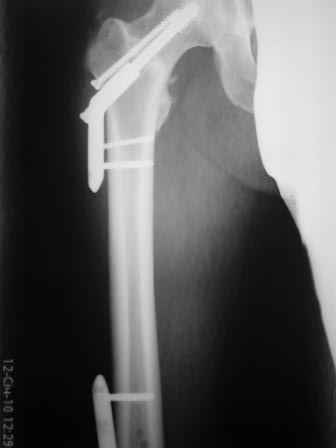

Больной, 30 лет, высокоэнергетическая травма 6 мес назад (базальный перелом шейки бедра + перелом дистального метаэпифиза бедра на той же ноге по типу 33-С2). Практически сразу же был произведен МОС шейки системой DHS (Synthes), через две недели - МОС дист.отдела бедра системой LISS (Synthes)плюс костная пластика с крыла подзвдошной кости.

На сегодняшний день наступил перелом пластины, укорочение бедра 2 см. Перелом шейки клинически и рентгенологически сросся. Больной астеничен, немного анемичен. Рентгенограммы прилагаются.